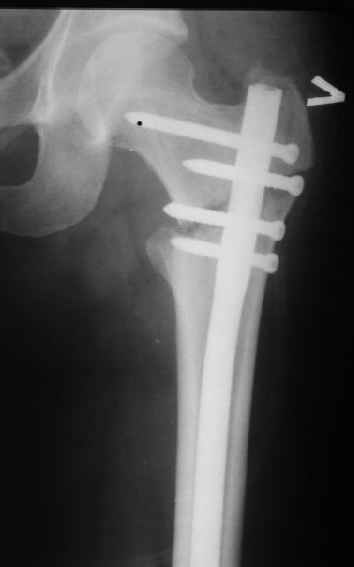

> При межвертельных переломах с цефаломедуллярными гвоздями бывает,

> что проксимальый винт проходит или черед периферический отломок, или

> прямо над ним. И если остался диастаз, то этот винт при осевой

> нагрузке не дает сблизиться отломкам. Пример остеосинтеза в застарелом

> случае в приложении. В качестве предупреждающей меры можно долотом

> разрушить латеральную стенку дистального отломка под винтом.

Конечно, мы не синтезируем остеопорозые вертельные переломы согласно прилагаемому примеру, винты 6 мм вырежутся. Но у более молодых при хорошем качестве кости такие или подобные гвозди с поперечным расположением винтов вполне применимы для меж- и подвертельных переломов.

Это было года 2,5 назад, мы тогда еще уточняли возможности шинирования с угловой стабильностью гвоздем с поперечным расположением винтов при переломах проксимального отдела бедра. Пациенту не пришлось приобретать намного более дорогой рекон или проксимальный гвоздь. В приложении еще несколько примеров применения того гвоздя при высоких переломах бедра, в том числе с более латеральной точкой входа. Гвоздь изгибаем для этого.